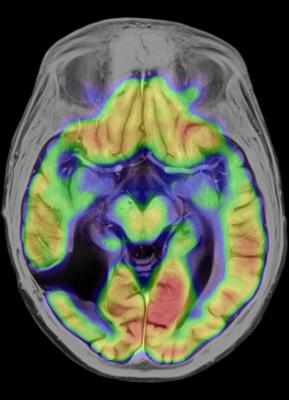

June 12, 2015 - Neuroinflammation caused by a reactive immune system could be tripping off the neurodegeneration seen in certain dementias, multiple sclerosis and other deadly diseases of the nervous system. A novel molecular imaging technique could be the key to understanding how best to treat these and other devastating diseases, according to a recent study presented at the 2015 Annual Meeting of the Society of Nuclear Medicine and Molecular Imaging (SNMMI).

At the heart of this maladaptive immune response are microglia, immune cells in the central nervous system that can be activated to trigger neuroinflammation. For this study, researchers used positron emission tomography (PET) to measure activation of microglia by employing a molecule from E. coli bacteria called lipopolysaccharide (LPS), or endotoxin. LPS stimulates the immune system and is accompanied by a radiotracer called carbon-11 PBR28 (C-11 PBR28). This form of molecular imaging allows the minimally invasive visualization of neuroinflammation. C-11 PBR28, is injected and binds to translocator proteins expressed on activated microglia. A PET scanner can then detect the radioactive particles emitted from inside the brain, representing areas of increased microglial activation before and after immune stimulation with LPS.

"The imaging technique could shed light on the immune dysfunction that underpins a broad range of neuroinflammatory diseases, such as Alzheimer's disease, depression, post-traumatic stress disorder and addiction," said Christine Sandiego, Ph.D., lead author of the study and a researcher from the department of psychiatry at the Yale School of Medicine in New Haven, Connecticut. "This is the first human study that accurately measures this immune response in the brain. The discoveries made with this technique could contribute to promising new drug treatments."